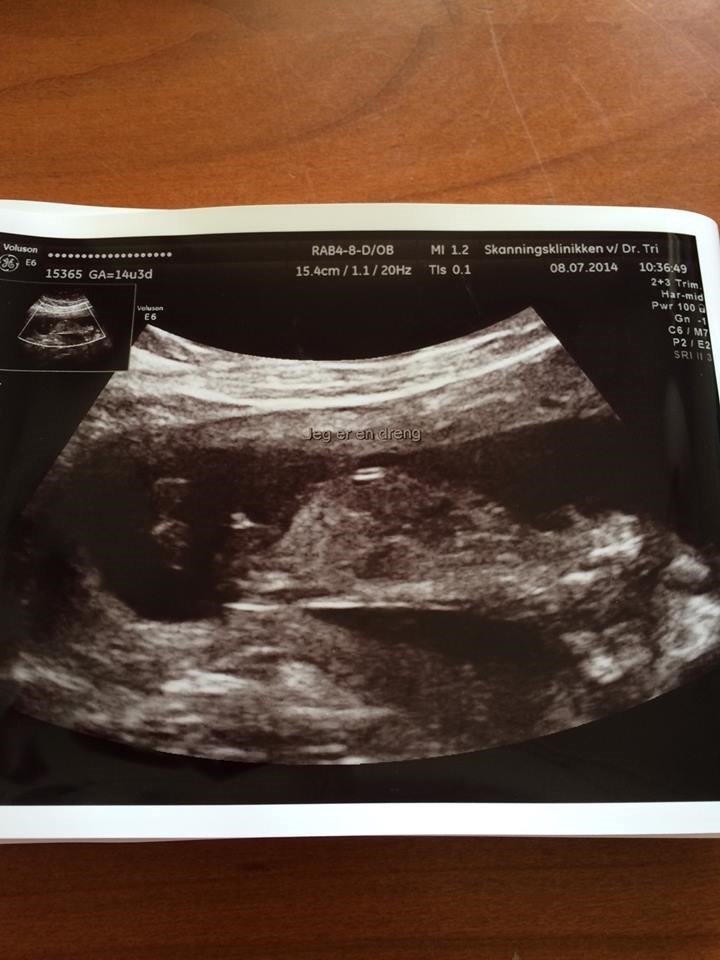

Jeg har os det her billed ved ikke om du kan se det bedre her?

Vedhæftede fotos (klik for at se i fuld størrelse)

Det er uden tvivl en dreng

Der kan man se det er en dreng

Er også sikker på det er en dreng